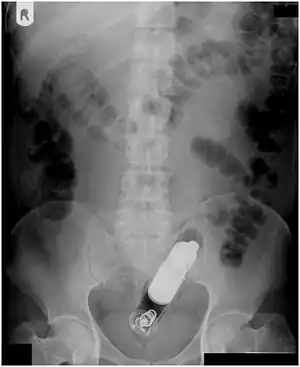

Abdominal X-ray showing small packages of cocaine swallowed by a trafficker.